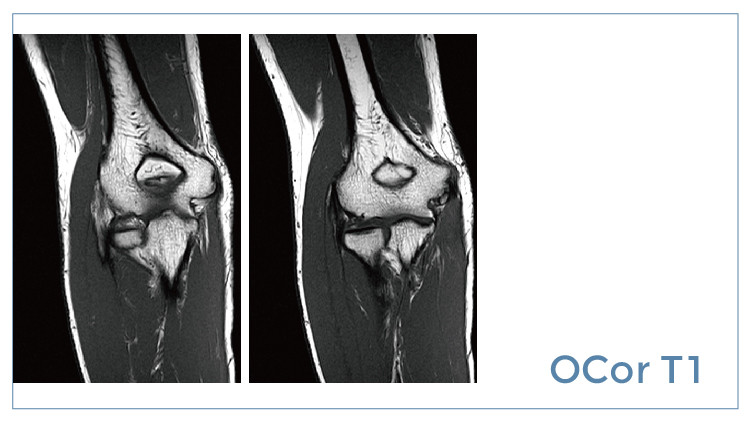

【朗润影像档案】磁共振影像病例分享(编号20190726)